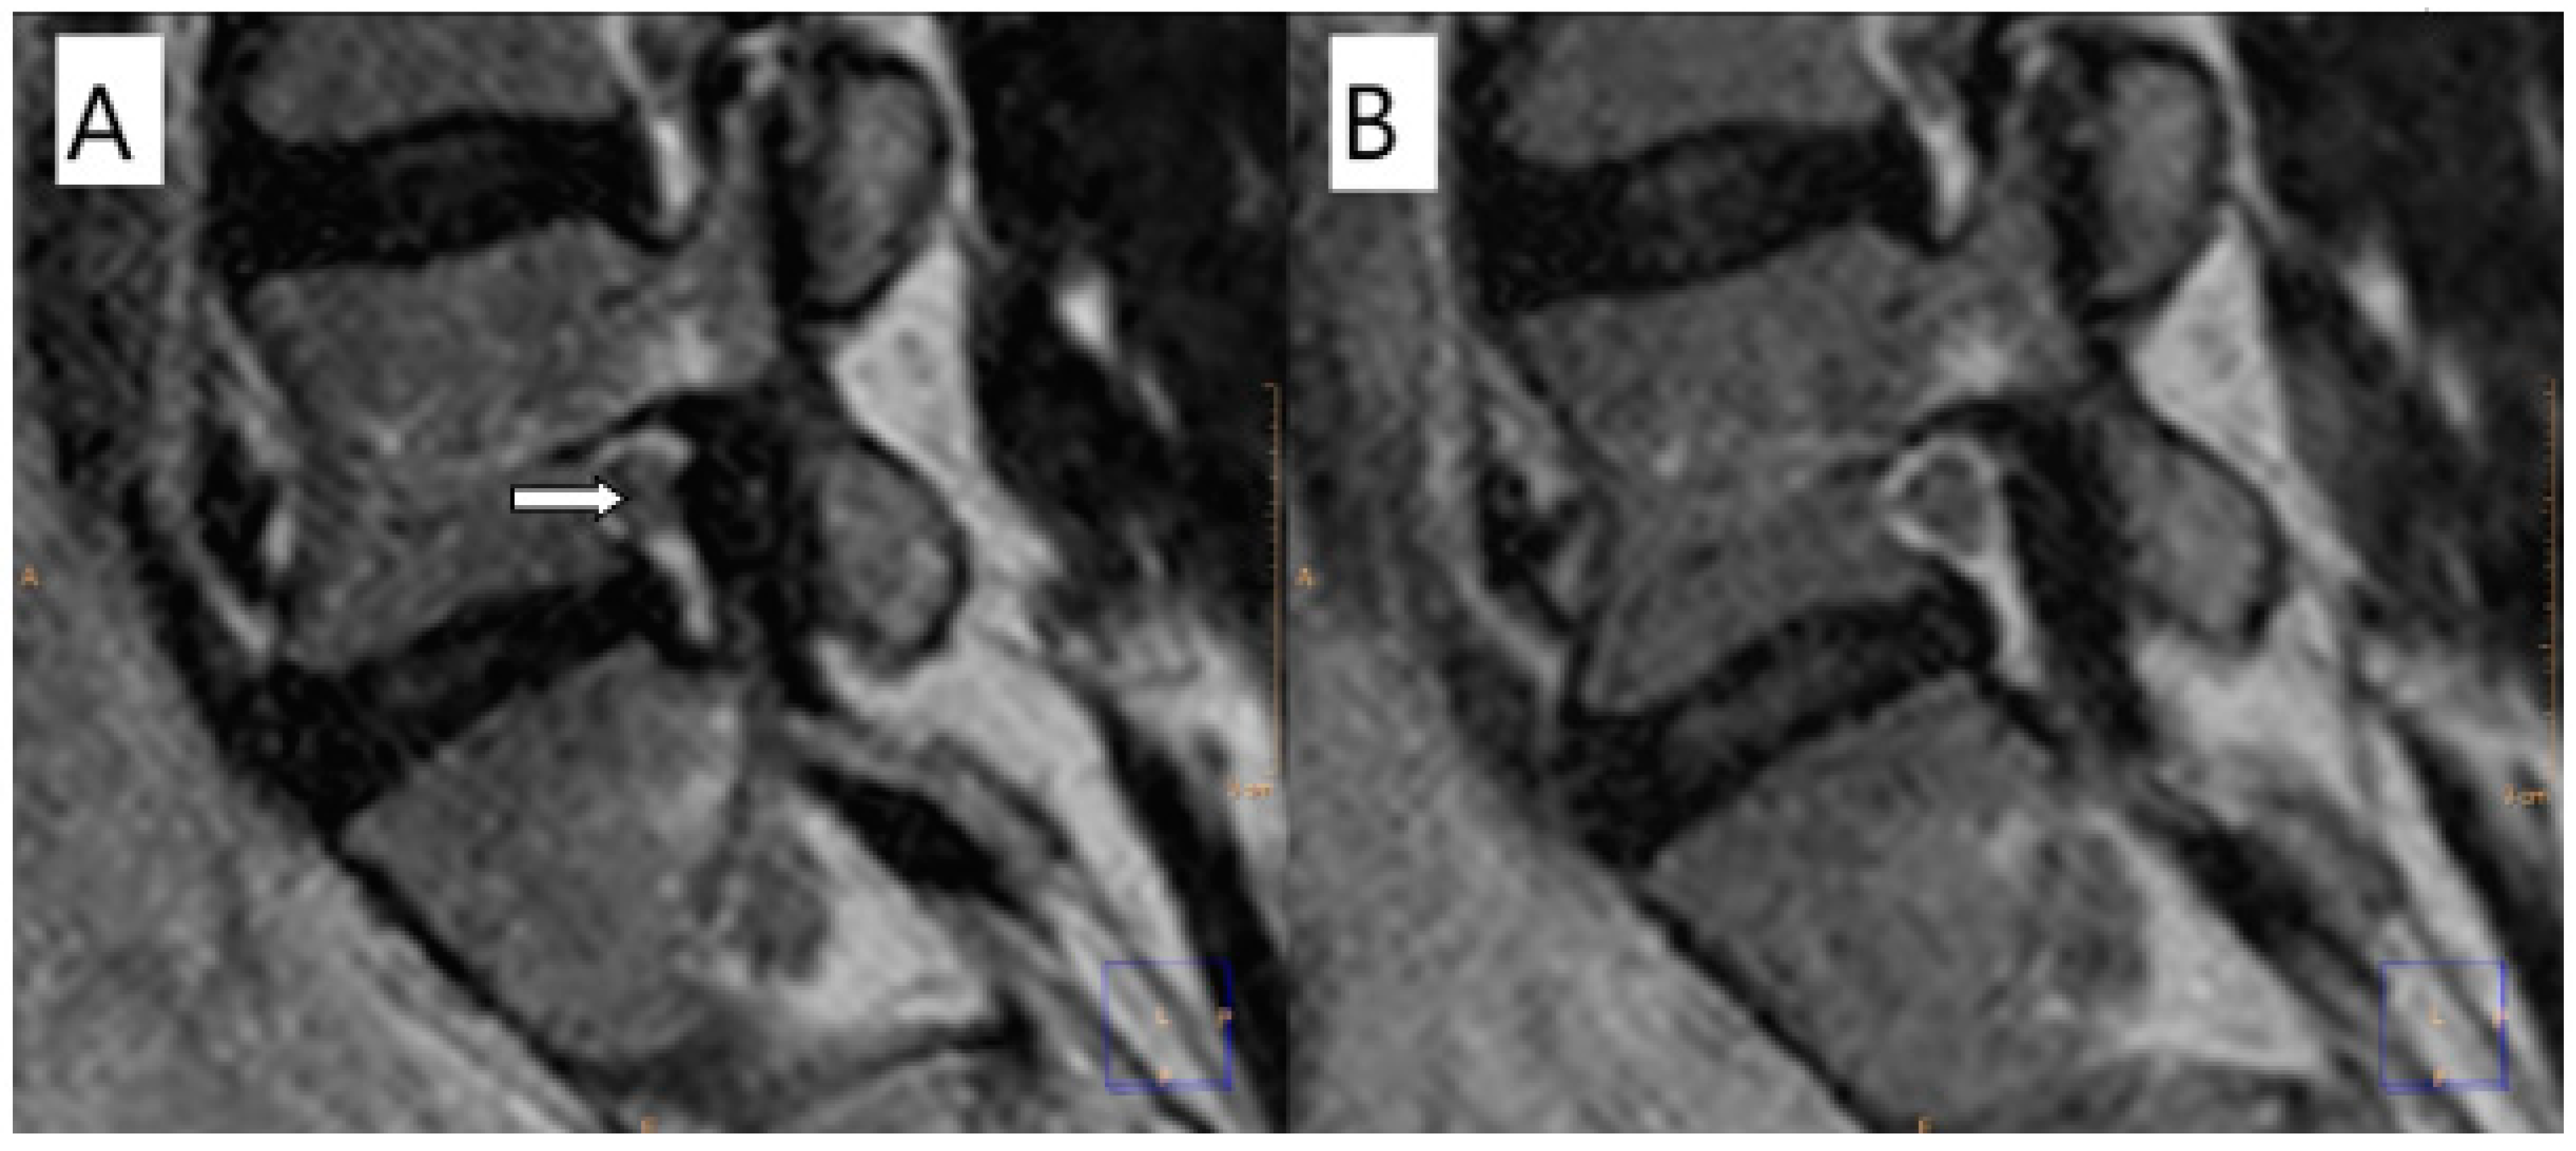

2.2. Image Analysis